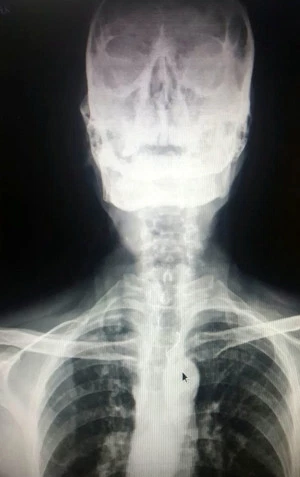

Hoảng sợ và đau đớn, ông vội vàng chạy đến bệnh viện để tìm cách chữa trị. Sau khi chụp X quang, các bác sĩ đã kết luận ông này đã nuốt phải chính hàm răng giả của mình.

Bác sĩ Shrinivas Chavan trả lời phỏng vấn rằng: "Trong khi kiểm tra phim chụp X của ông Kuber, các bác sĩ đã nhanh chóng nhìn thấy phần răng giả với các dây chằng bằng thép không gỉ đang nằm kẹt trong cổ họng của bệnh nhân".

Phim chụp X-quang của ông Kuber cho thấy ông đã nuốt phải một phần hàm răng giả của chính mình.